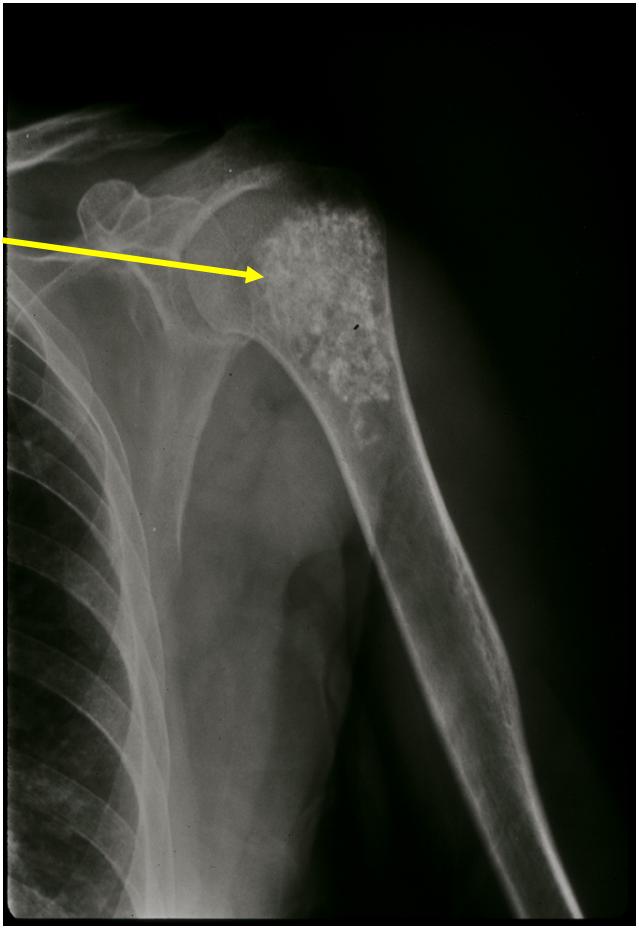

- Proximal Humerus, Femur most common long bones

- Localized, radiolucent defect usually with punctate calcifications

- Calcifications are typical but not always present

- Matrix may demonstrate various degrees of calcification

- Calcifications are stippled, punctate, popcorn like calcifications and “Ring and Arc” calcifications

- Cartilage tumors grow in a lobular manner. The perimeters of the lobules undergo

- enchondral ossification that may calcify. If the entire perimeter of the lobule calcifies it appears

- radiographically as a “Ring”. If a portion of the perimeter of a lobule calcifies it forms an “Arc” on

- an X-ray.

Plain X-Ray:

- Geographic lytic lesion

- Central often metaphyseal in long bones

- Chondroid matrix with calcifications in majority of tumors

- Approximately 20% have limited or no calcifications